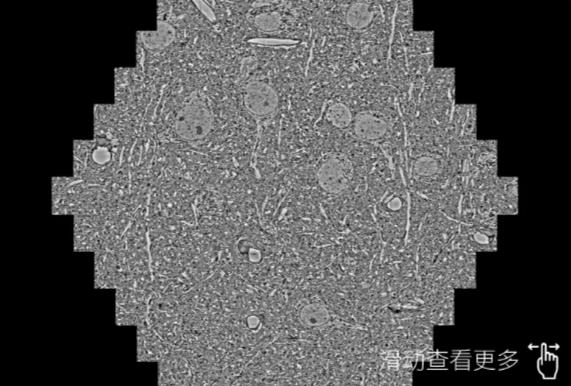

鼠脑切片。左图使用济南蔡司济南扫描电镜MultiSEM706对165μmx143pm面积区域成像,耗时仅需1.5秒。右图为鼠脑切片中30μm区域放大效果。样品由芝加哥大学B.Kasthuri提供。

使用蔡司高速济南扫描电镜MultiSEM对1mm²人脑皮层组织进行高分辨成像,并对其中的各种细胞结构进行三维重构分析。左图展示了2x3mm²组织平面中锥体神经元的三维重构效果。右图显示了局部体积神经元三维重构。图像由哈佛大学chtman实验室提供,渲染图由D. Berger 制作。